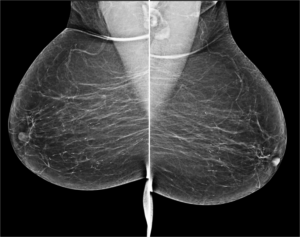

Cranio caudal view: Focal cluster of punctate microcalcifications seen in left sub areolar region- Indeterminate. On Tomosynthesis: In the given slice of tomosynthesis the calcifications are clearly seen and also the skin pores are well made out in the same section which confirms that the calcifications are in the plane of skin. Hence the calcifications are benign. No further views/ management required.